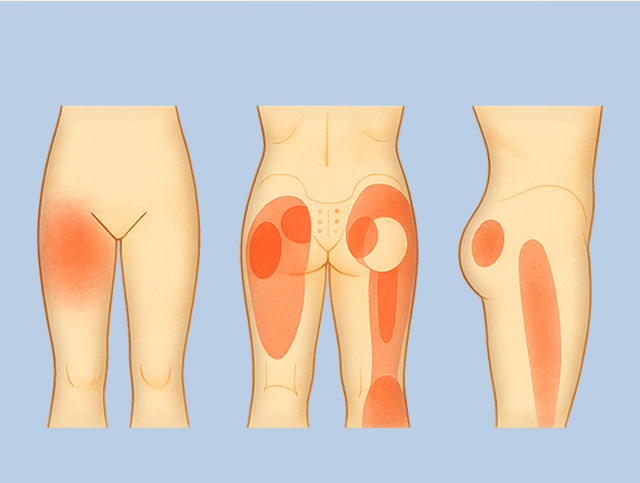

좌골신경통

좌골 신경에 염증, 손상, 압박이 발생하여 허벅지, 종아리, 발로 이어지는 통증

허리디스크나 척추관협착증, 이상근 증후군이나 근근막통증 증후군에 의한 발생이 많은 편

허벅지 근육 통증

허벅지 안쪽 내전근, 앞쪽 대퇴사두근, 뒤쪽 햄스트링 등 세부근육의 염증, 손상에 의한 통증과 보행장애 발생

과도한 운동이나 충격, 근육 긴장의 누적에 의해 주로 발생